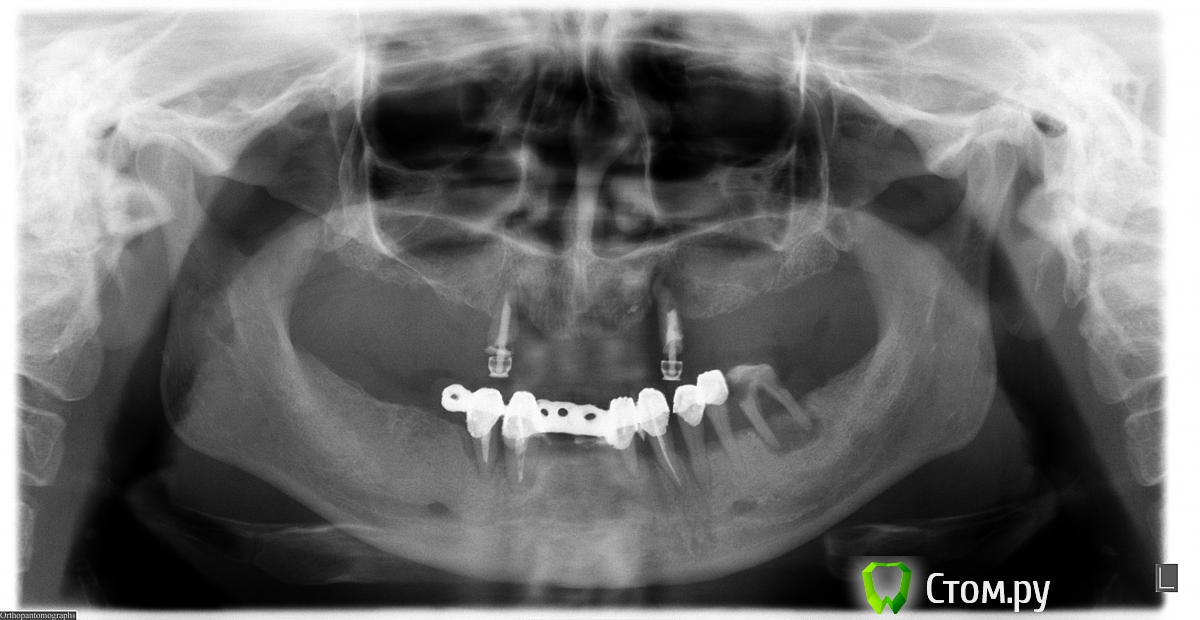

тяжелый случай Опубликовано 11 мая, 2014 Поделиться Опубликовано 11 мая, 2014 Уважаемые доктора! Что можно сделать в данном случае по протезированию на имплантах? Какие челюстно-лицевые манипуляции могли бы посоветовать? Какое необходимое кол-во имплантов нужно ставить? Какой металл для протезов? И еще очень важный вопрос: к кому из профи Москвы (клиника, хирург) вы посоветуете обратиться? 30 мая я буду в мск именно по этому вопросу. Это оч для меня важно - права на ошибку просто нет. Спасибо. Ссылка на комментарий

Bier Опубликовано 11 мая, 2014 Поделиться Опубликовано 11 мая, 2014 6-8 имплантатов на верхнюю челюсть + 2 синуслифтинга и 5-6 имплантатов на н.ч. совет в личке Ссылка на комментарий